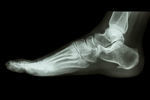

シーバー病/踵の痛み

【実例】シーバー病

「朝起きたら痛くて踵が着けなかった」と訴えます。